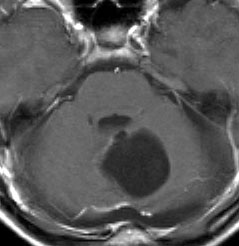

思春期の女の子にできた小脳腫瘍です。とても大きく見えますがほとんどが水たまり(のう胞といいます)。第4脳室が腫瘍で圧迫されて閉塞性水頭症になりました。のう胞の中に出血がありますが毛様細胞性星細胞腫では腫瘍内出血をしばしば見ます。右の写真で脳室が大きくなっています。こんなに大きいのに小脳症状は全くなくて,頭痛と嘔吐が症状でした。

赤で塗ったところだけが毛様細胞性星細胞腫です。これを取れば治ります。簡単な手術ですし後遺症も残りません。